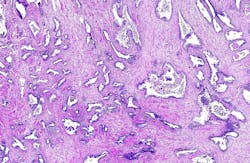

The study reviewed two national datasets to identify the health outcomes of men with prostate cancer, one of the most common cancers in veterans. The cross-sectional retrospective study included male patients first diagnosed with prostate cancer between the years 2000-2019. Schoen and his team analyzed datasets of 58,859 men from SEER (Surveillance, Epidemiology, and End Results) and 14,904 men from the Veterans Affairs Central Cancer Registry (VACCR).